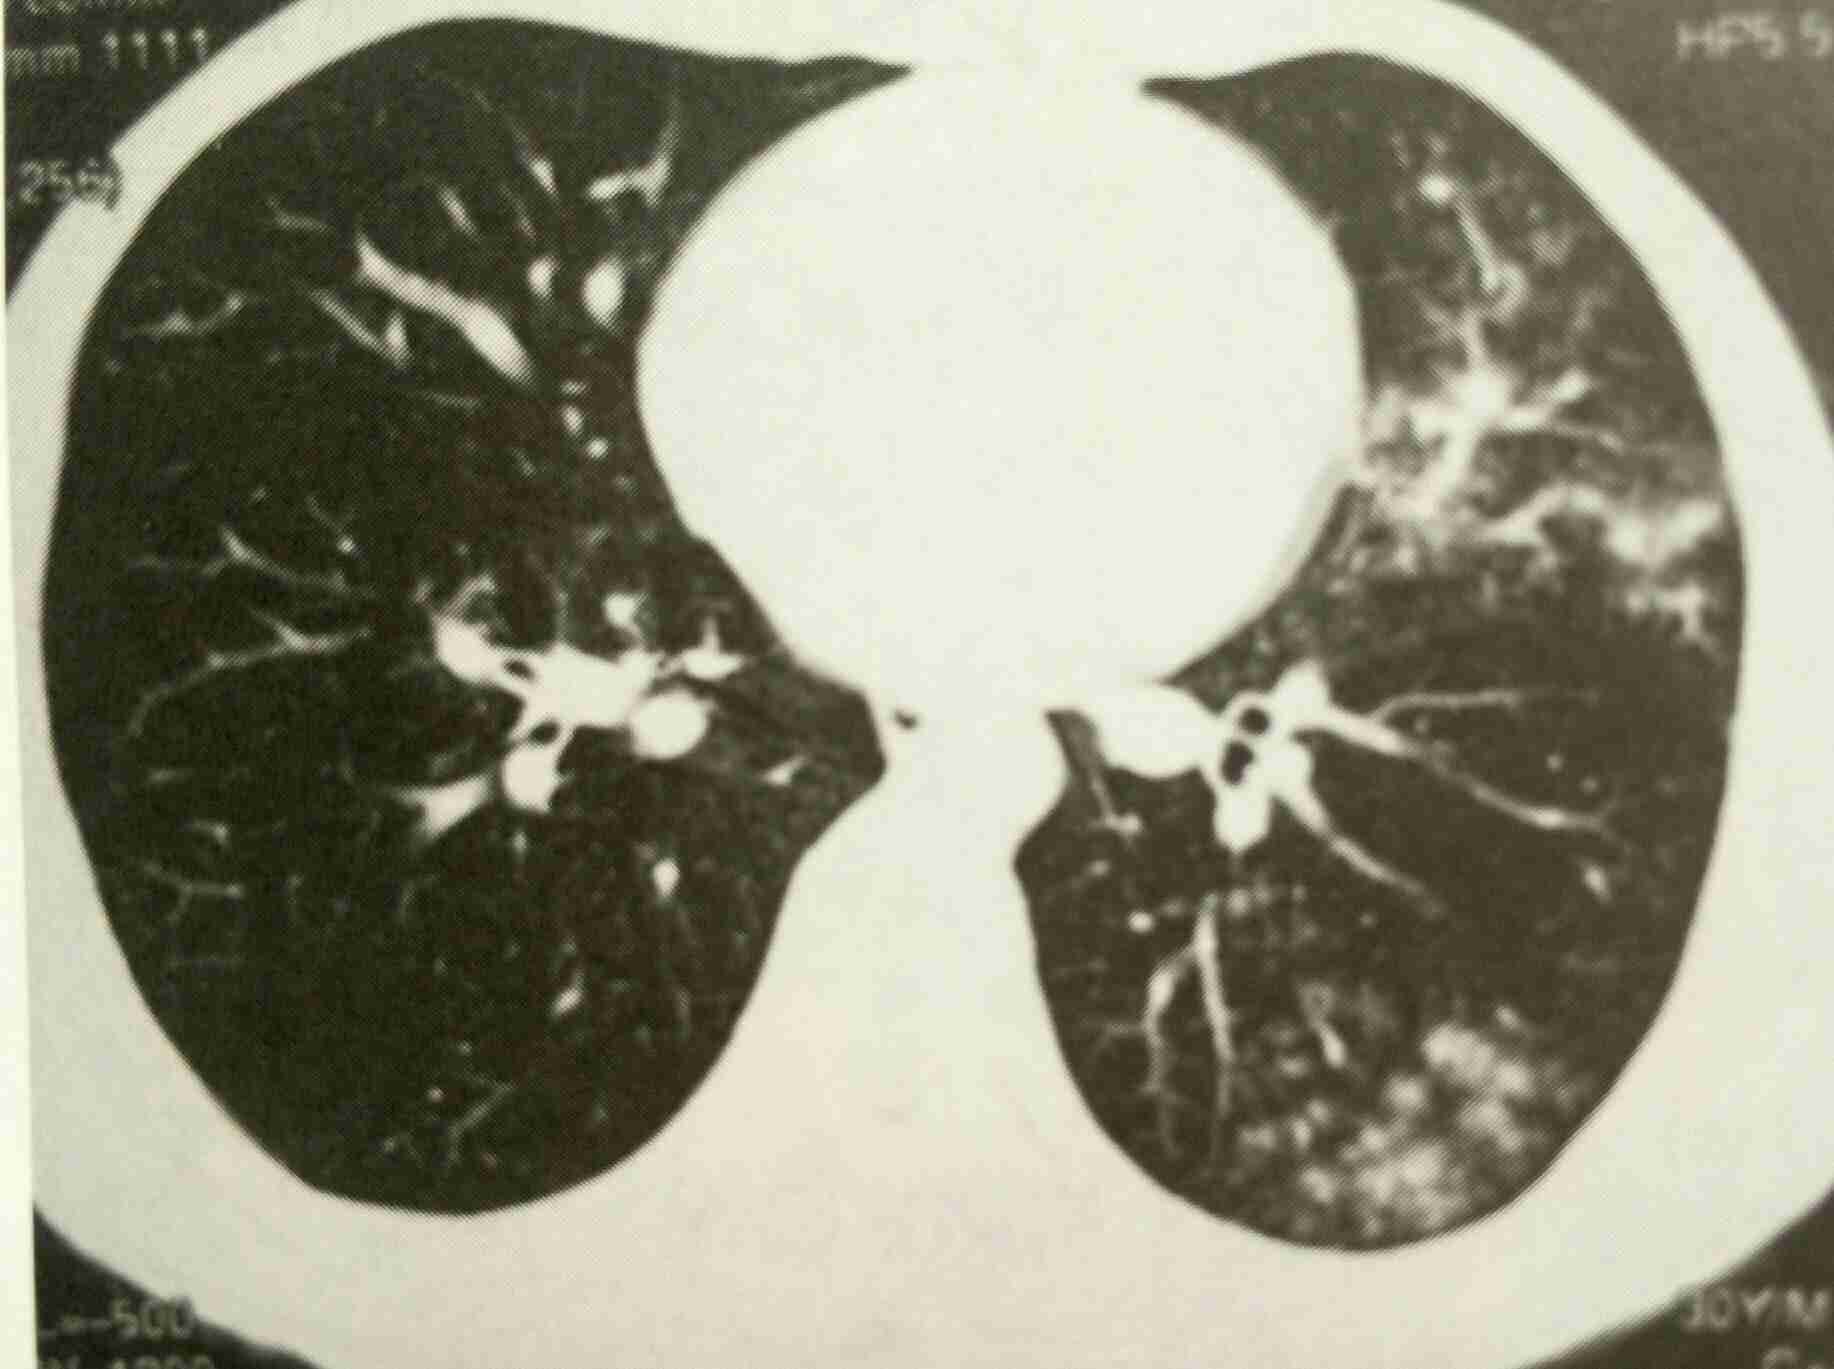

患儿,男,6岁,主因间断发热伴咳嗽5天入院。入院前4天在我院门诊治疗,初步诊断扁桃体炎,予口服阿莫西林克拉维酸钾片,每次1片,每日3次,小儿蒲地蓝口服液,每次1支,每日3次。服药一天后胸背部出现红色风团样皮疹,伴瘙痒,门诊肌注地塞米松注射液5mg后,皮疹消退。但仍间断发热,体温每日最少升高两次,最高39度5,咳嗽不明显,无痰,无呕吐,腹泻等,精神食欲尚可,大小便正常。查体:咽部充血,扁桃体无肿大,双肺听诊呼吸音略粗,未闻及干湿罗音,心腹无阳性体征,神经系统无阳性体征。化验血常规,白细胞14、5,中性粒细胞比例68%,淋巴32%,支原体抗体阳性。胸部正侧位片示:右上肺斑片状阴影。讨论一下本病例的诊断,治疗,及皮疹的原因。